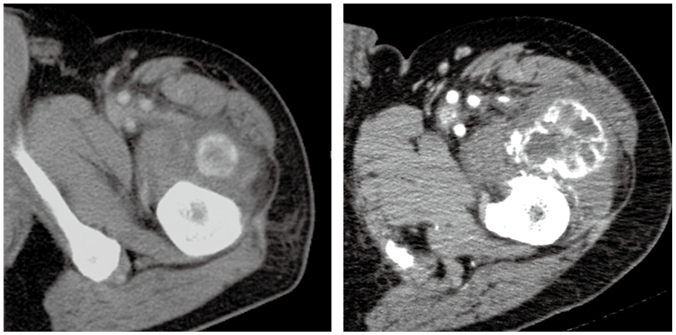

症例2

50歳代,男性。

約半年前から運動時に左大腿部の違和感が出現。徐々に疼痛を伴うようになってきたため受診。初診時(上段)および8カ月後(下段)のCTを示す。